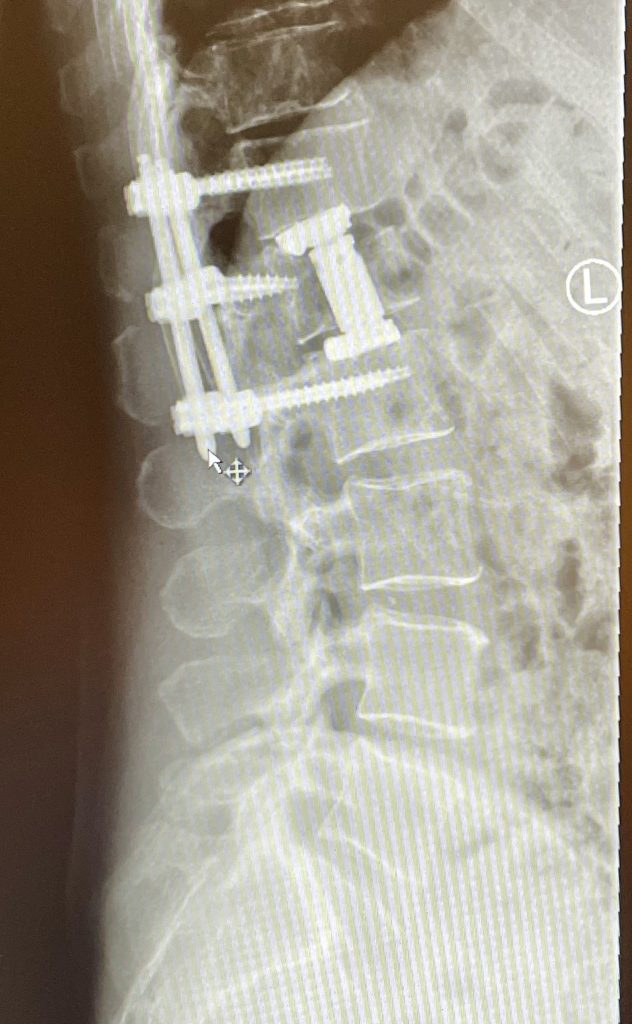

La cementación vertebral es un tratamiento contra el dolor, que consiste en introducir de manera percutánea cemento dentro de una vértebra fracturada, a través de una cánula. Previamente se intenta la corrección de la deformidad vertebral mediante el uso de unos balones hinchables.

La cementación vertebral están indicadas en pacientes con fracturas vertebrales osteoporóticas dolorosas , cuando no se toleren o estén contraindicado el tratamiento con corsé. Otras indicaciones serían las lesiones tumorales como por ejemplo el mieloma múltiple o ciertas metástasis.

En el caso de fracturas este procedimiento esta indicado dentro de los tres meses siguientes a la fractura (fractura reciente).